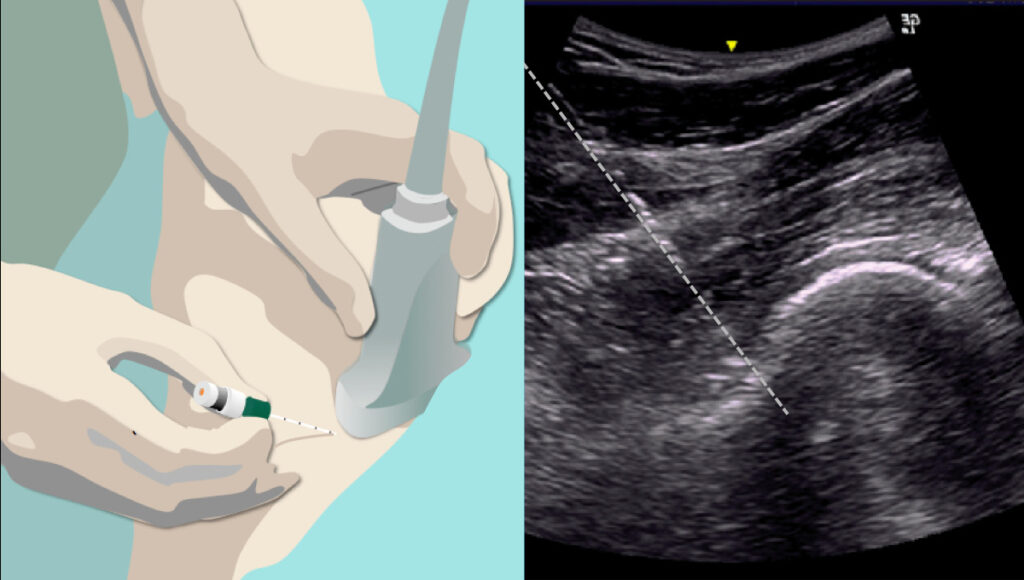

Infiltrazioni eco-guidate

Cosa sono? Le infiltrazioni sono delle punture comunemente eseguite da vari specialisti come ortopedici, fisiatri o reumatologi, per trattare il dolore delle articolazioni e nella